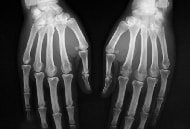

関節リウマチは、関節の変化をいち早く見つけることが治療の第一歩。診断にはX線検査が欠かせません。次のようなことを行うのに大変有効な方法です。

初期の診断には、通常は手と足のX線撮影を行います。さらに、痛む場所があれば、その部分の関節も撮影します。関節の変化は、ステージであらわしますが、各ステージはX線写真ではどのように写されるか、みてみましょう。

●ステージ1(初期)

滑膜の炎症は、関節のまわりの組織の影となって写ります。軟骨の変化が進むと(軟骨そのものは写りません)、関節の骨と骨が挟まくなって見えます。また、骨が薄く写ることがあります。骨粗鬆症の状態です。

●ステージ2(進行期)

病変が進むと、軟骨と軟骨が接する部分がさらに狭くなります。また骨の表面が削れる「骨びらん」が、虫食い状に穴があいたように写し出されます。

●ステージ3(高度期)

やがて軟骨が消失すると、骨の破壊がはっきあたりわかるようになります。亜脱臼・脱臼や変形のレベルを画像化して見ることができますので、手術法を探るときなどにも重要です。

●ステージ4(末期・荒廃期)

骨と骨がくっつき1つの骨のようになる「強直」や、骨がとけて骨と骨が離れる「ムチランス変形」の様子が写されます。